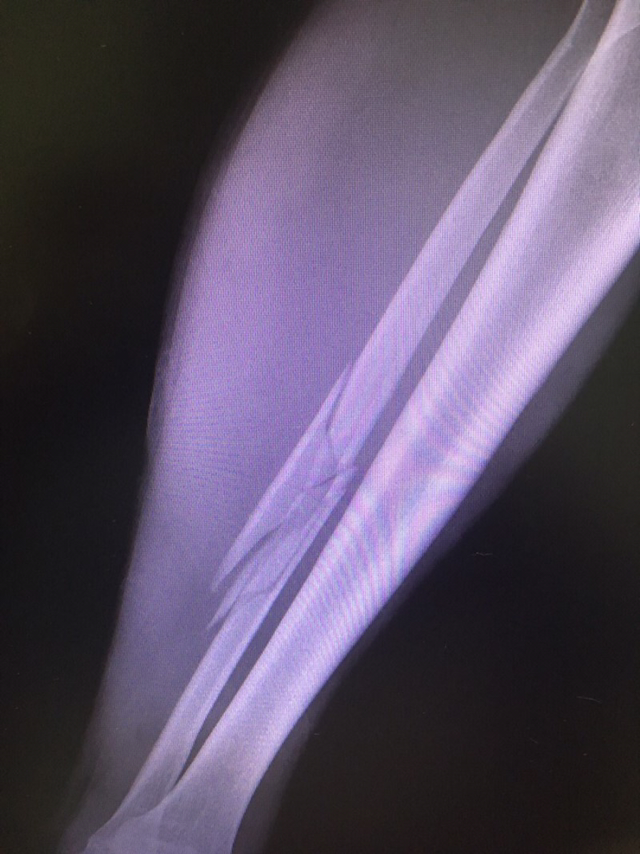

발이 아프다는 사내. 축구하며 태클 피하랴다 발목을 접질렸다고 했다. 대수롭지 않은 염좌이길 바라며 사진부터 찍어보았다.

오호 통재라. 종아리 비골이 촤르르 부러지셨네.